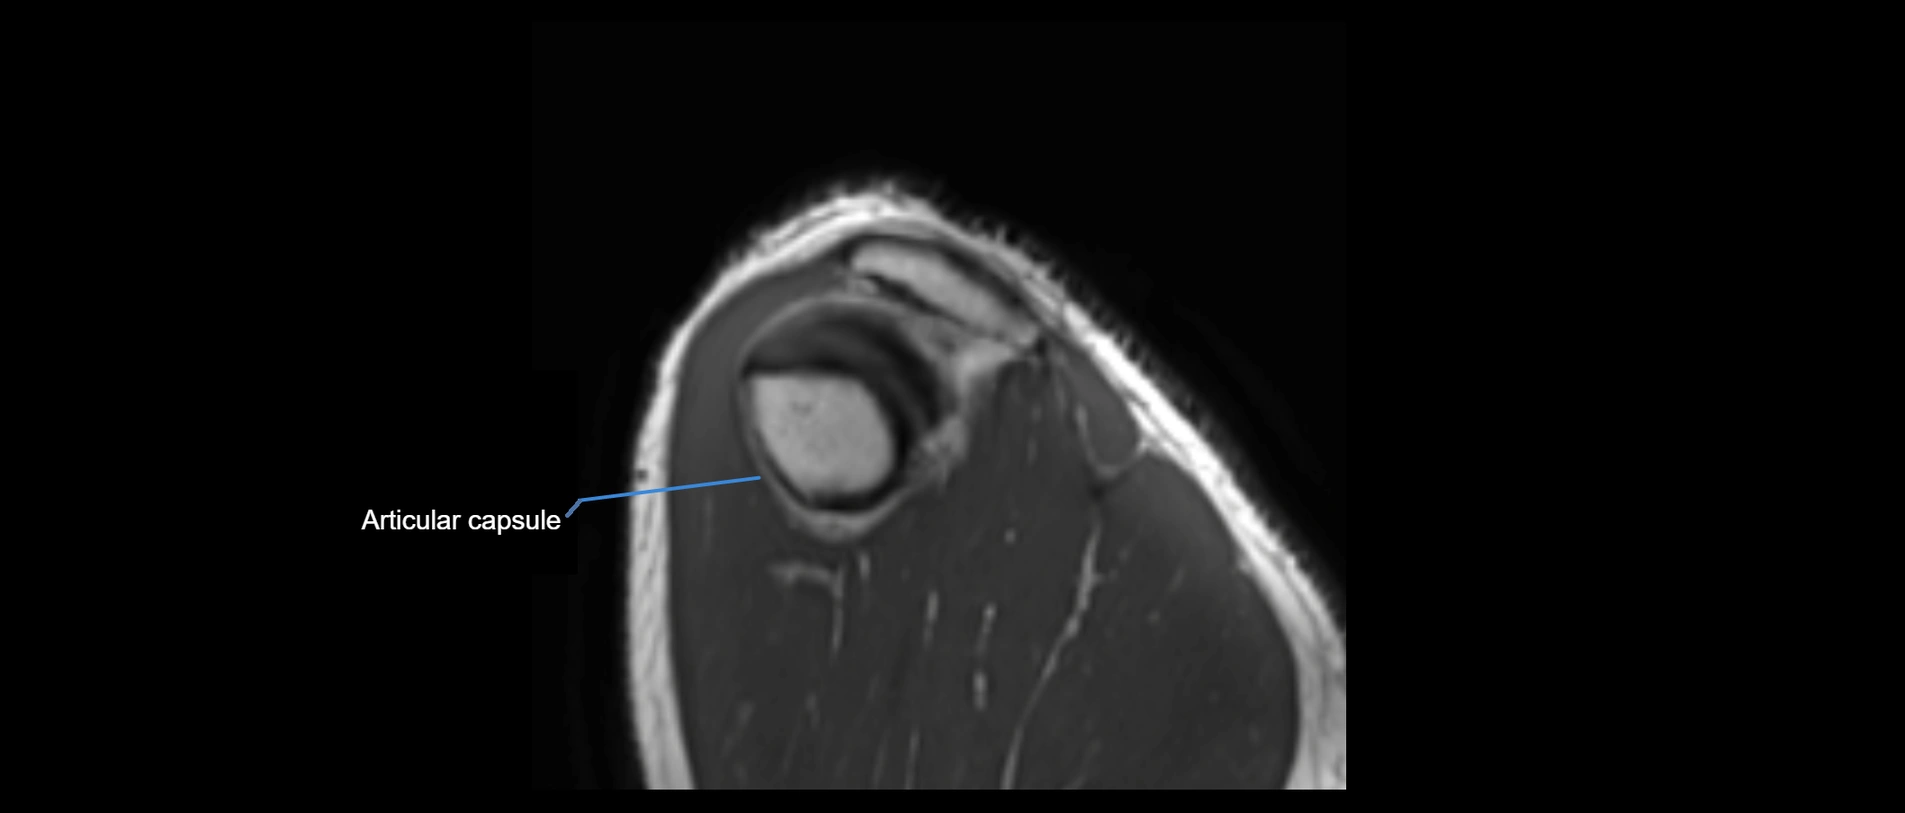

MRI images

image

MRI Appearance

• T1-weighted images:

• Normal ligament: Low signal (dark linear band) spanning acromion to clavicle.

• Surrounding fat planes: Bright, delineating the ligament clearly.

• Marrow of clavicle and acromion: Bright due to fatty content.

• Tears: Discontinuity or irregular thickening with intermediate-to-bright signal.

• Chronic injury: Thinning, fraying, or irregular low-signal fibers with adjacent scarring.

• T2-weighted images:

• Normal ligament: Low signal, homogeneous.

• Partial tear or sprain: Focal hyperintensity or thickening.

• Complete tear: Discontinuity with fluid-bright gap between clavicle and acromion.

• Associated edema: Bright signal in distal clavicle or acromion marrow.